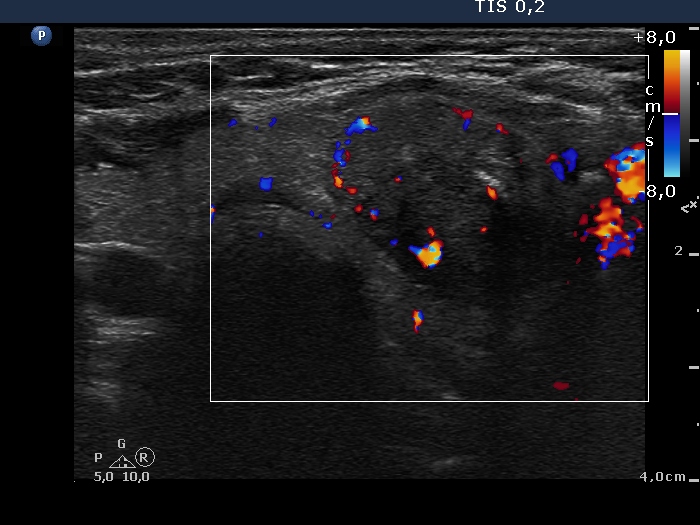

Intranodular hyperechogenic figures - case 1197 (ultrasonographic picture 9)

Lower part of the left lobe, transverse scan, color Doppler mode. The nodule presents intranodular flow and signs of perinodular vascularity.